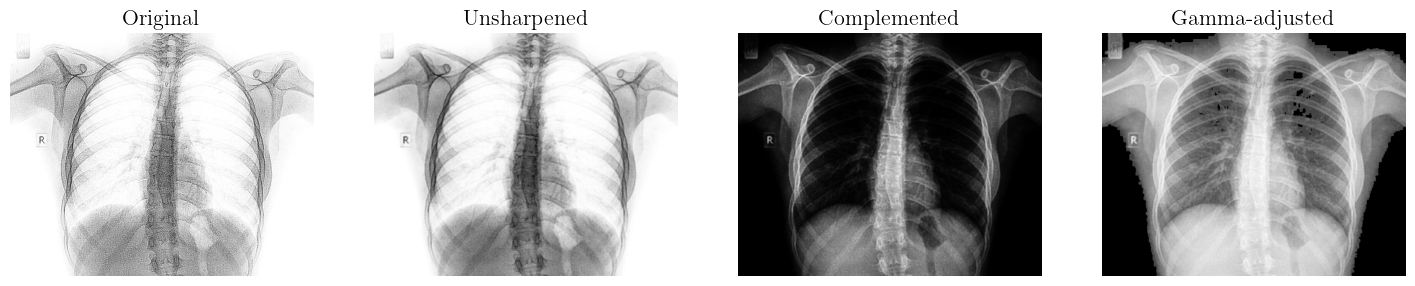

We applied a bidirectional pipeline designed to transform images between two visual states, such as from (image_1) to (image_2) and vice versa, using spatial enhancement techniques. This process involves applying image processing operations like filtering, sharpening, histogram equalization, or edge enhancement to modify spatial features such as contrast, texture, and detail [42]. In the forward direction (image_1 to image_2), enhancements might emphasize features like edges or brightness to highlight specific content. The reverse transformation (image_2 to image_1) uses inverse or compensatory techniques to restore the original spatial characteristics. Key to this bidirectional process is the preservation of structural information, allowing for meaningful reversibility. Adaptive methods may be employed to ensure transformations remain context-aware and minimize loss of detail or introduction of artifacts [43].

The forward pipeline (Image 1 to Image 2) comprises spatial enhancement techniques such as histogram equalization, sharpening, and contrast stretching. These operations are applied sequentially to improve image detail, enhance edges, and increase dynamic range, transforming (image_1) into a visually enhanced version (image_2) while preserving essential structural and contextual features. However, we applied unsharp masking, a technique that enhances edges by subtracting a blurred version of the image from the original. A kernel combines two filters: a low-pass filter (typically a Gaussian blur) to smooth the image and a high-pass filter to extract edge details. The final image is produced by adding a scaled version of the high-pass result back to the original image [44]. This enhances fine structures and sharpens transitions without significantly amplifying noise. The combined kernel thus balances detail enhancement and noise suppression, making unsharp masking effective for improving visual clarity in both natural and synthetic images [45].

Noise Amplification: Subtracts a Gaussian-blurred image (7 x 7 kernel) to isolate noise, multiplies by β[1.6,2.1]\beta\in[1.6,2.1], and adds back to the image. Parameters are optimized using a blended SSIM+NMI metric, achieving 76.10% similarity.

Figure 1: Proposed bidirectional image-to-image transformation pipeline. An adaptive SSIM+NMI module tunes parameters to ensure reversibility, minimize artifacts, and highlight scientific novelty in reversible spatial enhancement.

The reverse pipeline (Image 2 to Image 1) includes several operations aimed at approximating the original image (image_1) from the enhanced version (image_2). Gaussian blur is first applied using a 7×77\times 7 kernel to reduce high-frequency noise introduced during sharpening. Complementation follows, inverting pixel intensities to counteract contrast enhancement effects. Gamma correction is then used to adjust overall brightness, with

fine-tuning to reverse nonlinear intensity shifts. Despite these efforts, the reverse transformation achieves a maximum of 74.80% similarity, primarily due to irreversible information loss from noise amplification and detail suppression during the forward enhancement. A comparative analysis of the two images reveals that (image_2) is the complement of (image_1). Moreover, (image_2) exhibits increased noise levels, as well as differences in dynamic range and brightness relative to image_1. To generate (image_2) from (image_1), a spatial enhancement pipeline comprising several stages is employed. The pipeline includes the following operations:

This pipeline successfully synthesizes image_2 from image_1 while accommodating variations in noise, brightness, and dynamic range. Parameter optimization for each stage was conducted using the optimal_parameters() function, albeit via a heuristic approach.

The quantitative evaluation of the proposed transformation pipeline was conducted using a blended similarity index that combines the Structural Similarity Index (SSIM) and the Normalized Mutual Information (NMI). This hybrid metric jointly captures perceptual fidelity and information preservation, thereby providing a more comprehensive assessment of transformation consistency. For the forward pipeline (image_1 \rightarrow image_2), the framework achieved a blended SSIM+NMI score of 76.10%. This relatively high score indicates that sequential operations—including unsharp masking for detail enhancement, gamma correction for perceptual brightness balancing, intensity complementation, and controlled noise amplification—were effective in generating visually consistent and structurally reliable outputs. The preservation of edge sharpness and global luminance distribution underscores the robustness of the forward transformation process.

In contrast, the reverse pipeline (image_2 \rightarrow image_1) achieved a score of 74.80%. The slight reduction reflects cumulative information loss introduced by noise amplification and nonlinear intensity mappings, which hinder perfect reversibility. Despite this, the reverse transformation still demonstrates acceptable fidelity, suggesting that essential structural and statistical properties of the original image are largely preserved. These results highlight the forward pipeline’s efficiency for enhancement tasks while emphasizing the inherent challenges of fully reconstructive inverse transformations in noisy imaging environments.